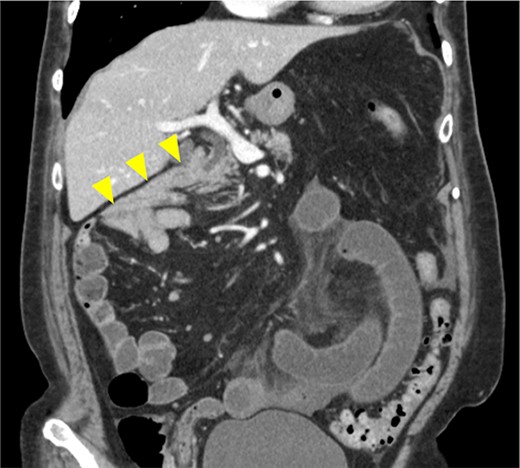

Image from enhanced CT. Contrast-enhanced CT shows the absence of a horizontal duodenal leg and the duodenum running caudally to the jejunum (arrowhead).

Upper-gastrointestinal contrast and CT findings facilitate the diagnosis. A typical finding of malrotation is the absence of a horizontal duodenal leg and leftward migration of the superior mesenteric vein relative to the superior mesenteric artery [10]. A right PDH is characterized by a dilated loop of small intestine that forms a localized cluster in the right upper abdomen and appears to be encased in a sac-like structure [10]. In our case, the ileum outside the hernia sac was strangulated and ischemic, whereas the jejunum inside the hernia sac was not ischemic. Therefore, abnormal findings in the hernial sac were not noticeable, and it was difficult to make an accurate preoperative diagnosis of a right PDH. On a CT scan obtained 4 years earlier, the jejunum was located in the abdominal cavity. It was thought that the jejunum had migrated to the inside of the hernial sac through the orifice and was strangulated (Fig. 4b). In cases of right PDH with malrotation, strangulation of the intestinal tract may occur both inside and outside the hernial sac, but strangulation outside the hernial sac is rare. Indeed, there are only three published case reports of a right PDH with malrotation and strangulation necrosis outside the hernia sac, including our case, except for volvulus [11, 12].